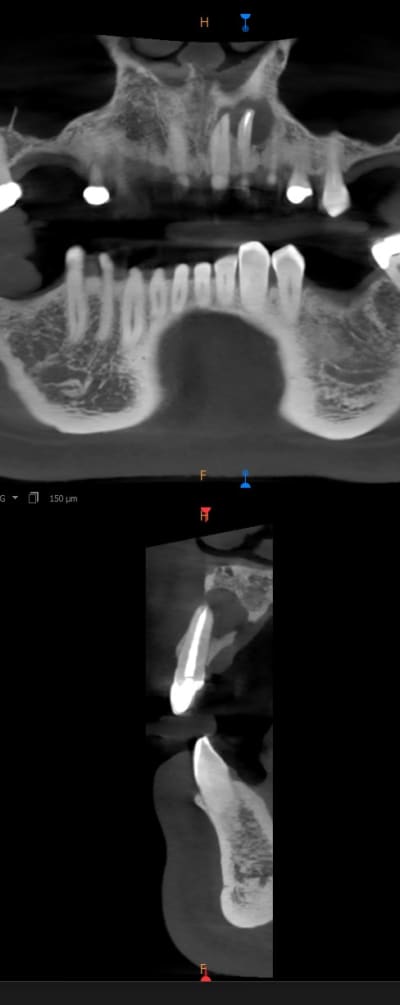

Bon, je viens de le revoir après 10 semaines.

J'ai coupé la racine, comblé avec du sticky bone de Medpark, je n'ai fait qu'une rétro hier, à la radio cela semble bien mais j'ai eu un soucis de nécrose partielle du lambeau juste après et on en est là. Aucune mobilité mais la 21 est en carton pour lui, bref perte de sensibilité.

Wacrap , au vu de la photo on dirait bien que le secteur 2 ant est en surcontact :

les dents paraissent plus en avant ,

la ligne des collets est plus haute

et la 11 et la 12 sont rabotées par une compensation en allant à droite .

C est quoi qu il y a sur la 22 une couronne , une mylolyse , ou les 2 ?

Ca vaudrait le coup de soulager les pression occlusales secteur 20 .